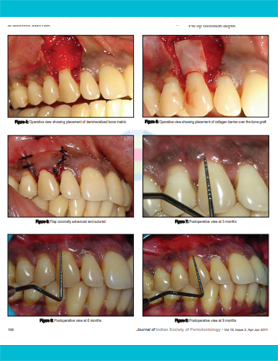

Periodontal Tissue Regeneration (2019)